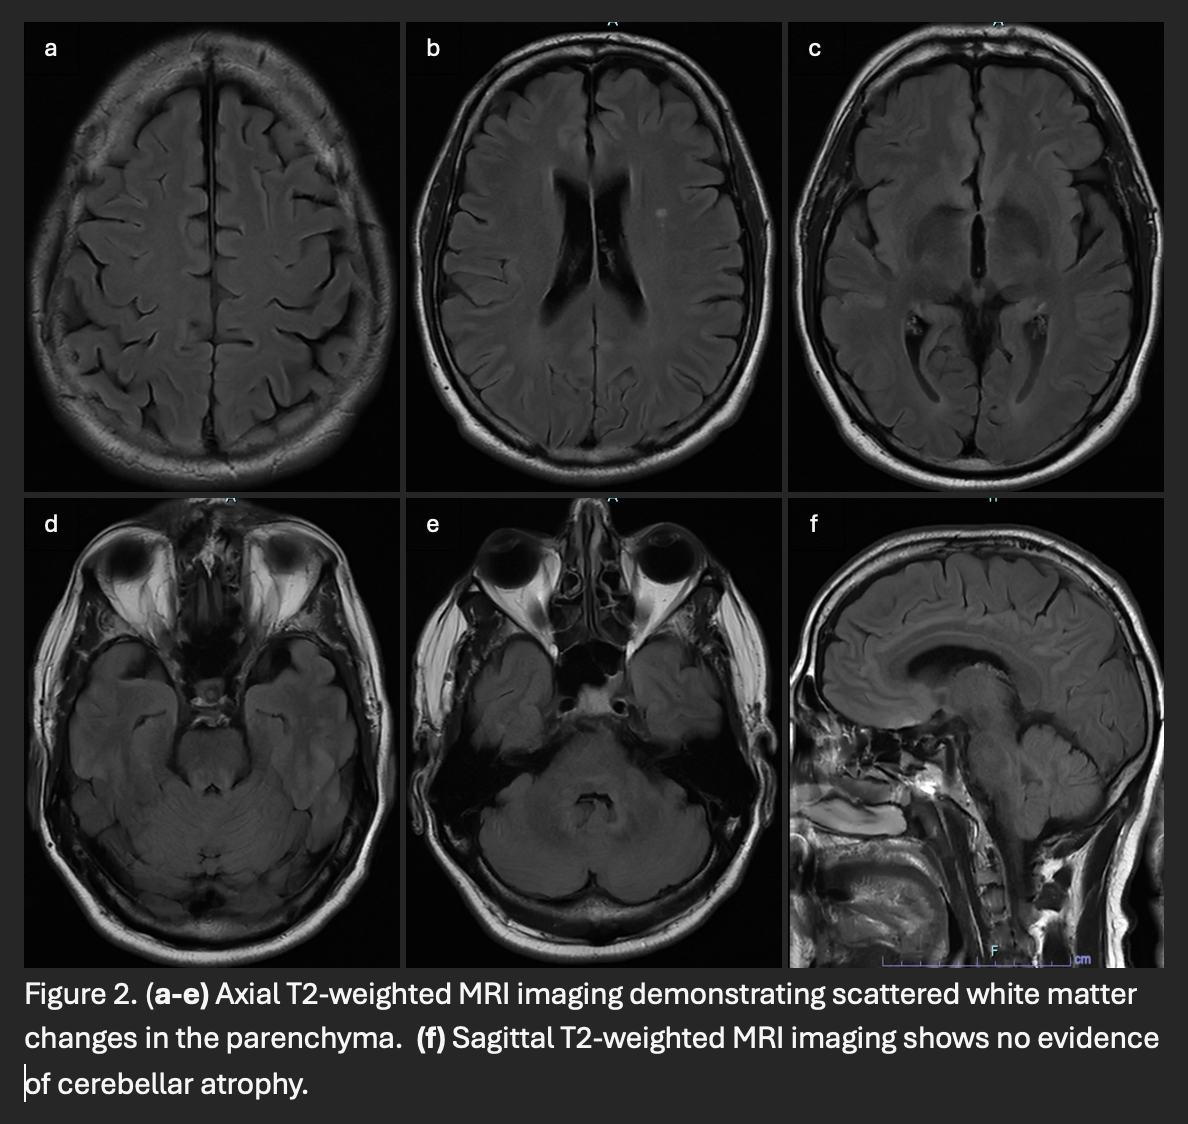

Results: A 60-year-old man presented with a year-long history of progressive ataxia, dysarthria, dysphagia, and fatigue. Three years prior, he developed diabetes insipidus due to a pituitary lesion [Figure 1], initially thought to be lymphocytic hypophysitis. Extensive ataxia workup, including autoimmune, paraneoplastic, genetic testing, FDG-PET, and DaT scan, was unremarkable. Three months later, jaw pain led to a biopsy-confirmed LCH diagnosis, retrospectively linking it to his pituitary lesion. Despite progressive cerebellar symptoms, brain MRI showed only nonspecific white matter hyperintensities, lacking characteristic ND-LCH findings [Figure 2]. He was treated with vemurafenib (480 mg BID), though dose reductions were required due to side effects. After 13 months, ataxia stabilized, but dysphagia and dysarthria worsened. A trial of high-dose methylprednisolone (1,000 mg daily for three days) provided no benefit.

Figure 2